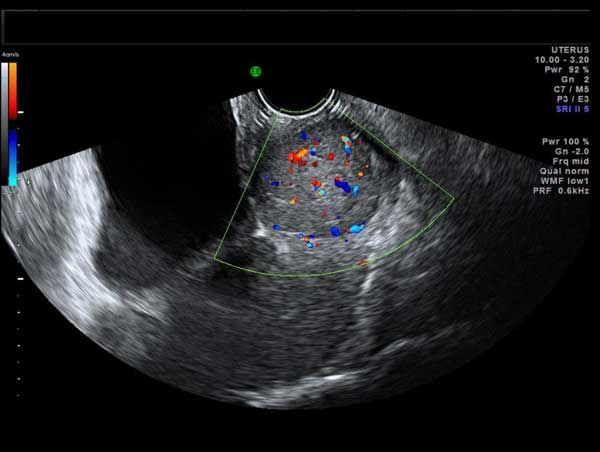

This 53 year-old woman has a uterine lesion and irregular bleeding. Which of the following is the correct diagnosis?